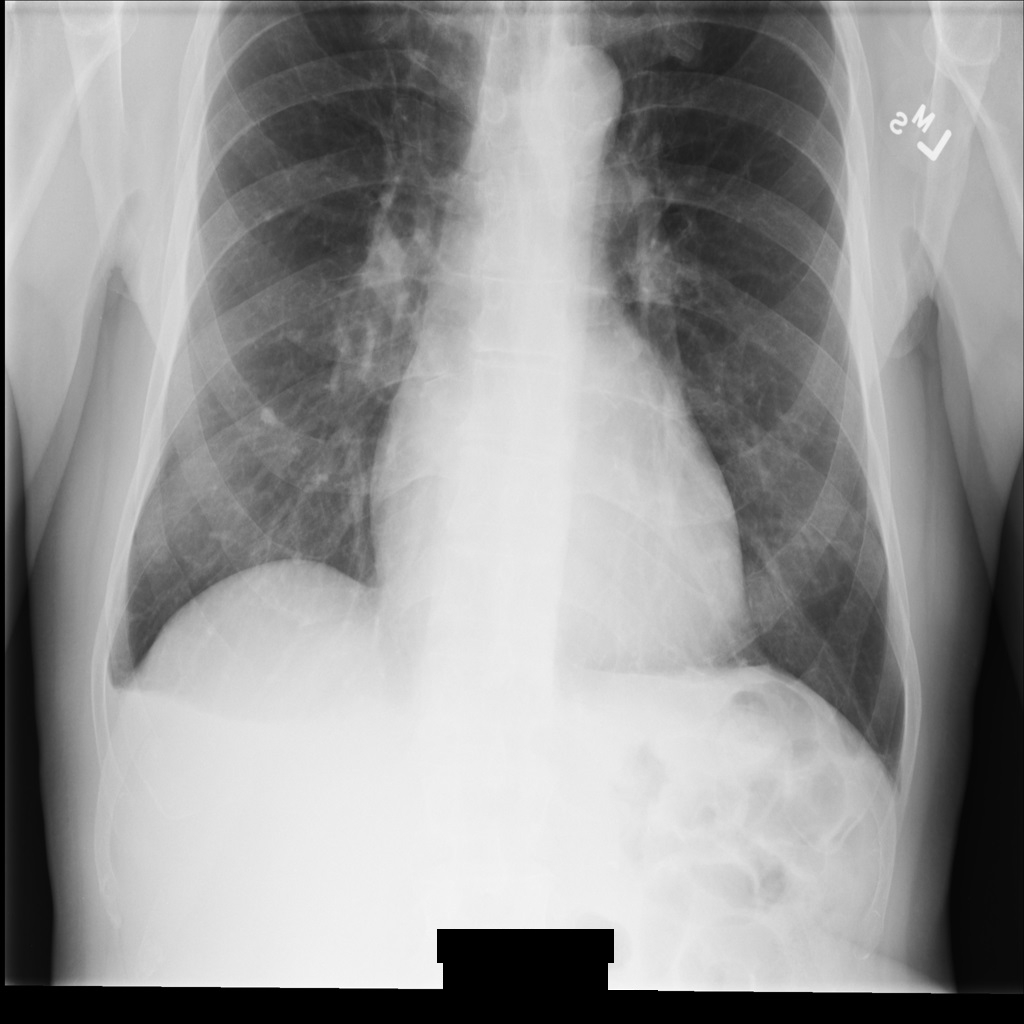

Les sections suivantes montrent à quoi ressemble l'image dans l'instance DICOM et les métadonnées de l'instance.

Exemple d'image

Certains exemples de cette page contiennent une sortie de l'image anonymisée. Chaque exemple utilise l'image d'origine suivante comme entrée. Vous pouvez comparer l'image de sortie de chaque opération d'anonymisation à cette image d'origine pour voir les effets de l'opération :